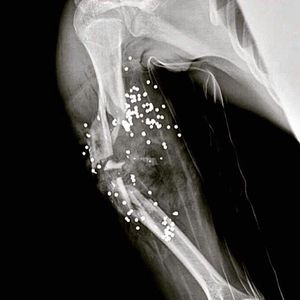

X-ray of shotgun victim, notice the pellets inside the wound and the damage they caused fracturing the humerus; this indicate the victim was shot in close range nearly amputating his whole arm of his body. @medicalcortex #medstudent #nurse #doctor #radiology #xray #trauma #premed #f4f #l4l #usmle #pathology #autopsy #surgery #emergencyroom #emergency #surgeon #orthopedic #medicine #follow #medical